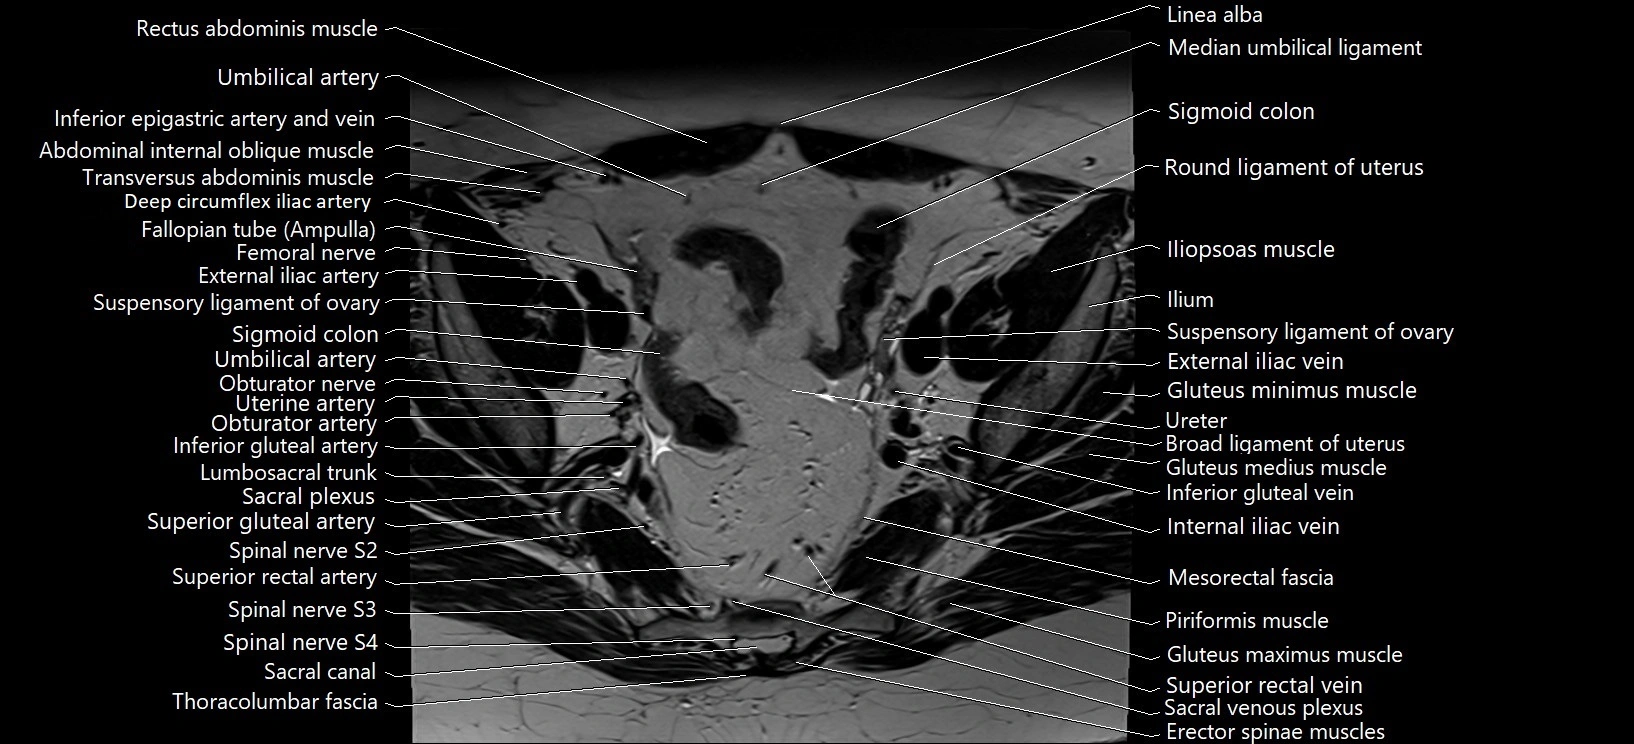

- Broad ligament of uterus

- Fallopian tube

- External iliac artery

- External iliac vein

- Iliopsoas muscle

- Lumbosacral trunk

- Sacral plexus

- Mesorectal fascia

- Piriformis muscle

- Superior rectal artery